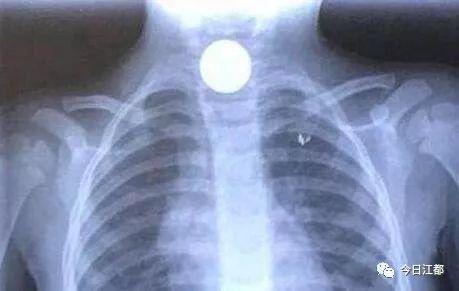

张月玲了解情况后,立即为孩子安排了胸部拍片检查,结果正如她所料,影片显示有金属物卡在幼儿食管上段的狭窄处。后经耳鼻喉科会诊,孩子被迅速转入耳鼻喉科病房,科主任肖旭东拿着片子认真看了起来,此时他心中不禁产生了一个疑惑,一般而言硬币都是圆形的,但在影片中显现的却是椭圆状,他大胆推测孩子可能误吞了不止一枚硬币。本来孩子的食管就细,这还卡住了多枚硬币,手术难度瞬间大增。